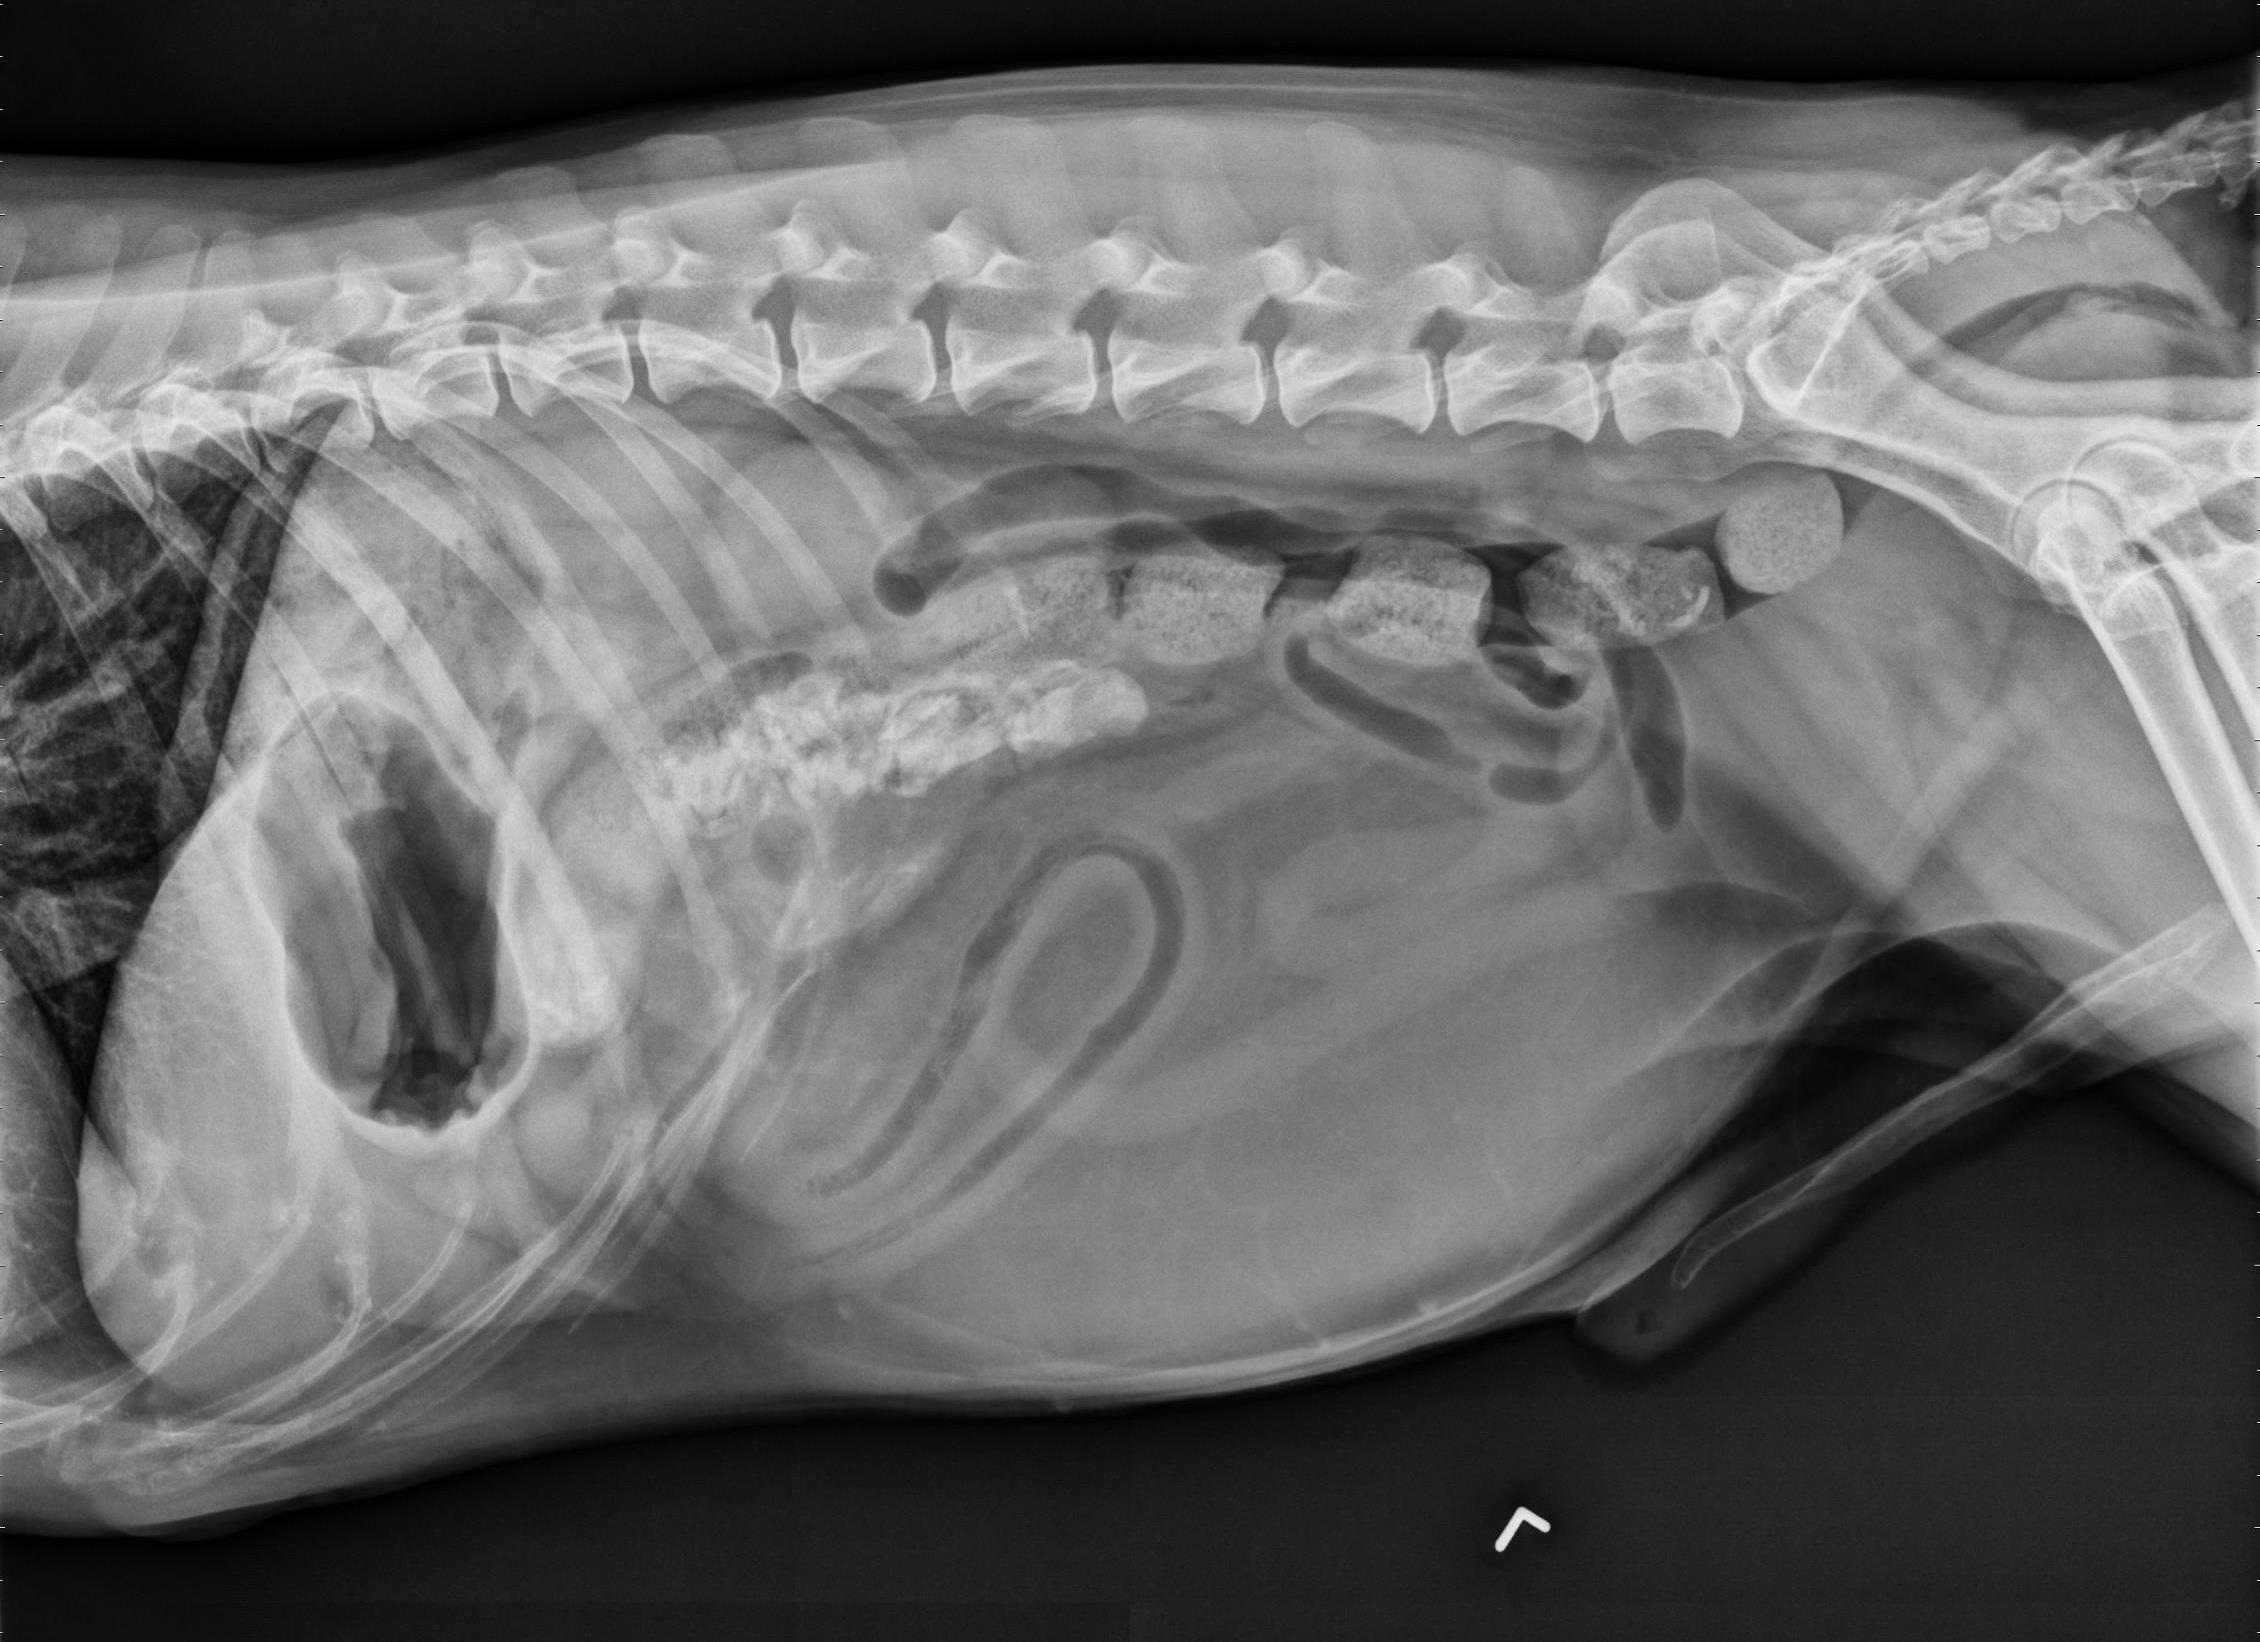

Er is een artefact door natte vacht langs de ventrale buik. De serosale details zijn normaal.

In het linker mid-ventrale abdomen bevindt zich een grote, ovale structuur met vetdensiteit van ongeveer 20 x 15 cm. Deze structuur veroorzaakt een laterale deviatie van de linker buikwand, een naar rechts en dorsaal verplaatste colon en dunne darmen, en een craniale verplaatsing van de staart van de milt.

De maag is matig met gas gevuld. De dunne darmen bevatten diffuus gas en vloeistof/weke delen densiteit en hebben een normale en uniforme diameter. In het colon zijn fusiforme tot rechthoekige botdense structuren zichtbaar.

Lever, milt, nieren en urineblaas zijn normaal.